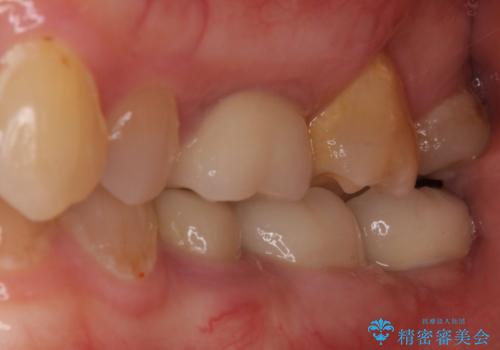

- 抜歯が必要と診断された奥歯の治療を希望して来院された患者様です。

一番奥の歯は歯根の一部を残した状態で、手前の歯とブリッジが装着されていました。

奥歯は歯根周辺の歯槽骨が広範囲に失われており、抜歯が必要と判断されました。

ブリッジの手前側の歯は、根管治療が必要な状態でした。

根管治療を行ったは、以前の治療で開けられて思われる穴が歯の内部に開けられており、炎症を起こしていました。

根管治療と合わせて、穴の開けられている部分を修復したところ、炎症による歯槽骨吸収に改善が見られました。

インプラント埋入にあたり、歯槽骨での炎症が広範囲であったことから、事前に骨造成を行いました。